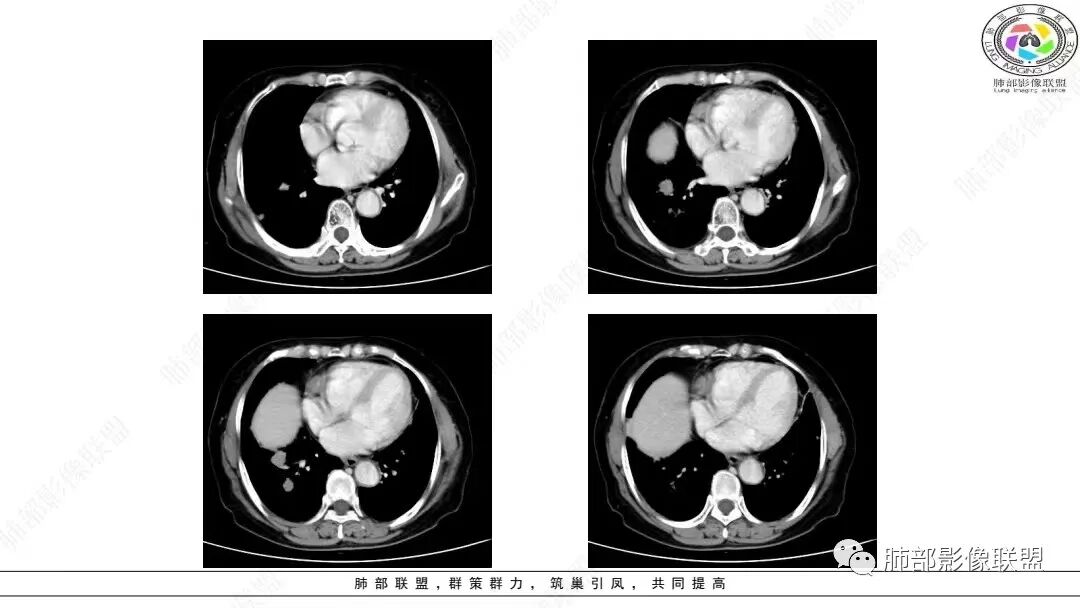

2.影像学特点:右肺上叶前段胸膜下不规则较大团块影,边界清楚欠光整,浅分叶,肺血管支气管出入,边缘膨隆胸膜凹陷具有一定张力,未见典型粗短毛刺,部分围以边界清楚的磨玻璃影,灶周小叶间隔增厚。块影密度不均,渐进性强化,可见砂砾样钙化,未见明显液化坏死或空洞。增强后病灶显示渐进性强化。MIP显示病灶内肺动脉穿行、并部分肺动脉受侵变细。纵隔及右锁骨上(胸廓入口)见肿大淋巴结。两肺可见多发大小不一的结节影,边界清楚,随机分布。

胸椎体溶骨性吸收破坏,突破骨皮质。腹部扫描未见肿块影。

大多数学者认为肺LELC患者易发生纵隔和肺门淋巴结肿大。本组68.44%患者伴肺门和/或纵隔淋巴结肿大,65.57%发生淋巴结转移,且淋巴结最大短径为(2.04±0.90)crn,提示以CT淋巴结最大短径1 cm为标准大致区分肺LELC患者淋巴结是否转移具有较高敏感度。

本组大部分病灶(64.75%)CT平扫密度均匀;增强后多数病灶以中度(71.75%)、渐进性强化(75.13%)为主,动脉期病灶内常见异常细小杂乱血管影(55.96%)。    笔者据此认为密度均匀且不易出现坏死、呈中度渐进性延时强化为肺LELC的特点,可能与病灶内部含有丰富的淋巴细胞浸润和大量纤维组织增生及胶质有关;病灶内部分细小杂乱血管影可追踪为支气管动脉,推测可能为新生肿瘤血管,提示肿瘤血供丰富,不易出现坏死;但新生肿瘤血管通常不成熟,血管通透性增高,致使对比剂外渗,使肿瘤表现为延迟强化。肺LELC生长较快时,由于血供不足,也可出现液化坏死及钙化等改变。肺LELC密度均匀、液化坏死较少及延迟强化,可作为其与肺鳞癌或腺癌的鉴别要点。